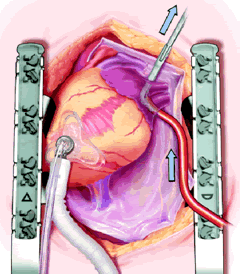

The right side of the pericardium is suspended with stay sutures, and the lateral pericardial attachment to the superior vena cava (SVC) is developed with cautery, allowing better exposure of the right pulmonary artery (RPA) and right superior pulmonary vein (RSPV). The thin pericardial reflection of the inferior vena cava (IVC) is developed, mainly with gentle digital dissection, exposing the posterior lying right inferior pulmonary vein (RIPV).

The plane between the RSPV and RPA is developed and a large bronchus clamp inserted between the two and gently manipulated between the IVC and RIPV. This manipulation should require NO force at all. The open end of a 16F Bard Red Robinson catheter is fed into the jaws of the clamp, and the clamp gently withdrawn, effectively isolating the right pulmonary venous drainage. It is important that the open end of the Robinson catheter is cephalad. Development of the interatrial groove is unnecessary.

Holding the closed Medtronic bipolar irrigated radiofrequency clamp in the surgeon’s left hand, the malleable clamp tips are gently curved outward. The lower jaw of the open bipolar clamp is placed into the open end of the Red Robinson catheter and the catheter gently withdrawn until the end is visible under the IVC. The catheter is removed and the clamp closed on the atrial side of the pulmonary vein/left atrial interface. Energy is applied until a transmural ablation is assured.